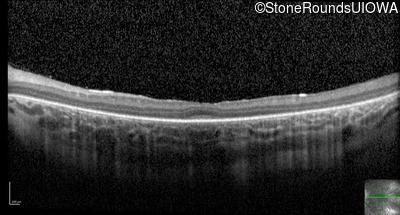

Optical Coherence Tomography - Right - 20/80 -1

Exemplar / OCT Stack